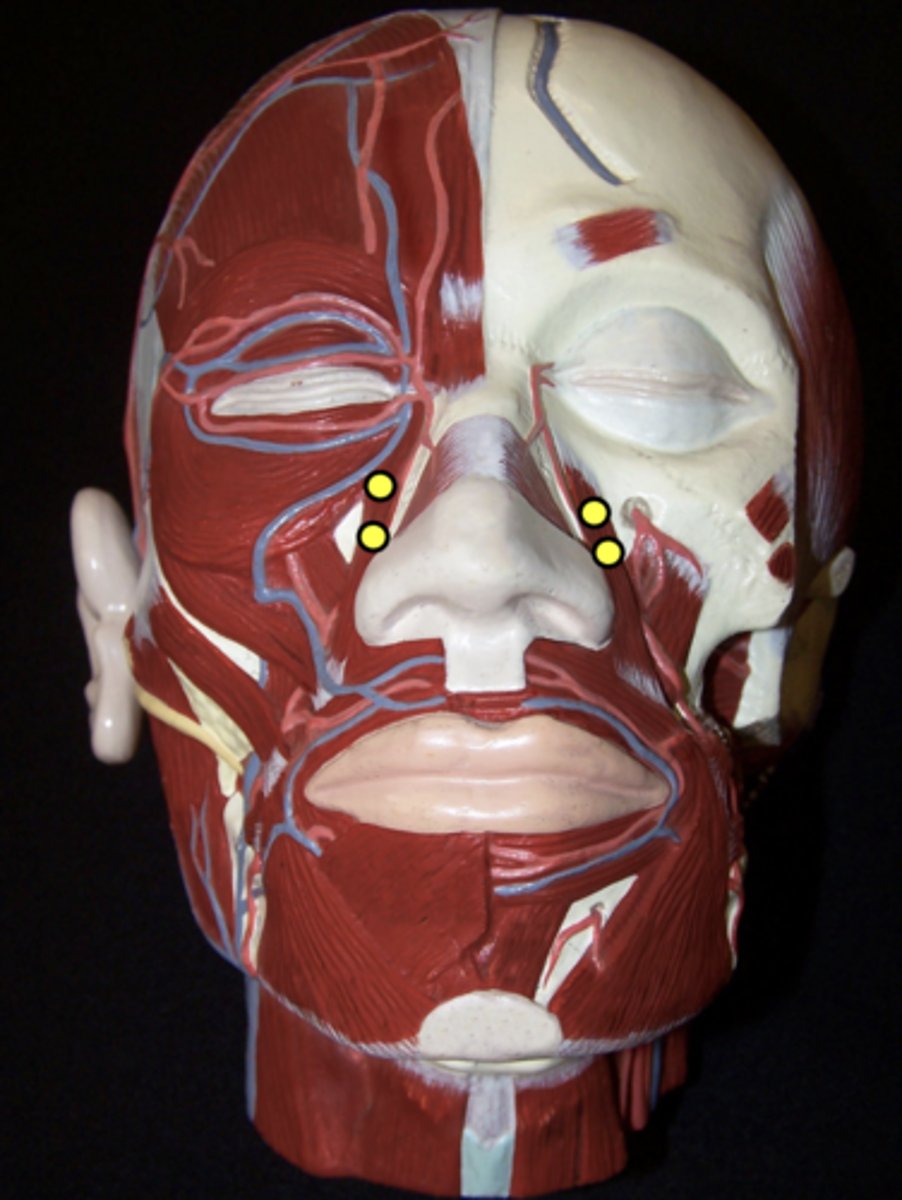

Zygomaticus Major

Zygomaticus Minor

Levator Labii Superioris